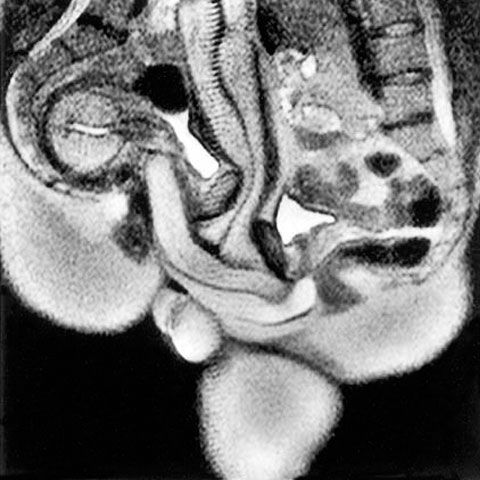

8 sept. 2009, 17:42Ultimele StiriUn cercetător olandez a realizat un film cu imagini RMN din timpul unui act sexual